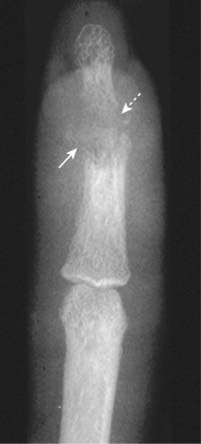

Figure 23-21 Septic arthritis and osteomyelitis, middle finger.

The hallmark of infectious arthritis, especially the pyogenic form, is destruction of the articular cartilage and long contiguous segments of the adjacent articular cortex from proteolytic enzymes released by the inflamed synovium. This patient has septic arthritis (the distal interphalangeal joint is destroyed) which has extended to the subjacent bone as osteomyelitis and destroyed either side of the joint space as well (solid and dotted white arrows). The time course of septic arthritis, unlike other arthritides, is usually quite rapid. This infection was the result of a human bite.